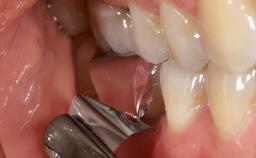

Peripheral Giant-cell Granuloma Associated with Peri-implant Tissues

Giant-cell granulomas (GCG) of the jaws are benign reactive lesions of unknown etiology, unrelated to giant-cell tumors (osteoclastomas), which are defined as benign but locally destructive and aggressive neoplasms (Jundt and coworkers 2005). Depending on their localization at the initial diagnosis, GCG are dived into central (CGCG) and peripheral (PGCG) types. CGCGs occur within the jawbones and appear as unilocular or multilocular radiolucent lesions. The incidence in the general population is very low. They are more commonly found in the mandible, mainly in children and young adults—patients are generally younger than 30 years—and have a greater incidence in females (Heithersay and coworkers 2002). The clinical behavior of CGCGs varies from slowly growing asymptomatic swellings to aggressive lesions that may result in pain, cortical perforation of the affected jaw site, and root resorption (de Lange and coworkers 2007).